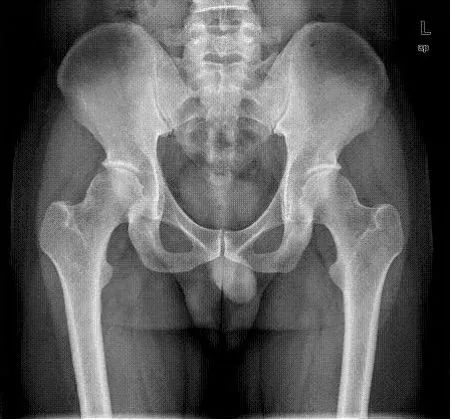

病例六:右侧股骨颈隐匿性骨折

男性,33岁,右下肢扭伤1周。

d-spect怎么检查【核医学科普】SPECT-CT全身骨显像wholebody bone scan给全身骨骼拍张“艺术照”_https://www.jmylbn.com_新闻资讯_第24张

d-spect怎么检查【核医学科普】SPECT-CT全身骨显像wholebody bone scan给全身骨骼拍张“艺术照”_https://www.jmylbn.com_新闻资讯_第25张